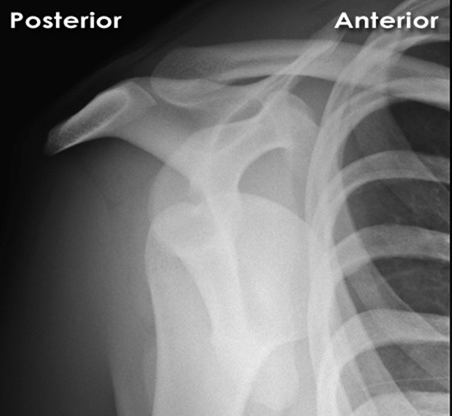

Correct Answer: Abducted and externally rotated

Explanation:

In a typical anterior shoulder dislocation, the humeral head rests anteriorly and inferiorly to the glenoid. The arm is consequently held in a position of slight abduction and external rotation, as attempts to internally rotate or adduct the arm cause significant pain and resistance. This is the hallmark clinical presentation.